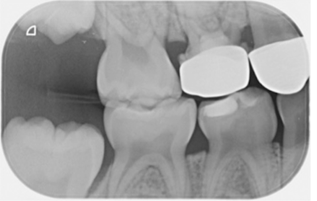

31. What option cannot be selected for the tooth # 3.6?

32. What options cannot be seen in the print of this X ray?

33. What options cannot be seen in the print of this X ray?

34. What option can be selected for tooth # 4.6?

35. What options cannot be selected for the tooth # 1.5?

36. What options cannot be selected for the tooth # 3.7?

37. What options can be selected for tooth # 1.2?

38. What option can be seen in the print of this X ray?

39. What options can be selected for the print of this X ray?

40. What cannot be seen in the print of this X ray?